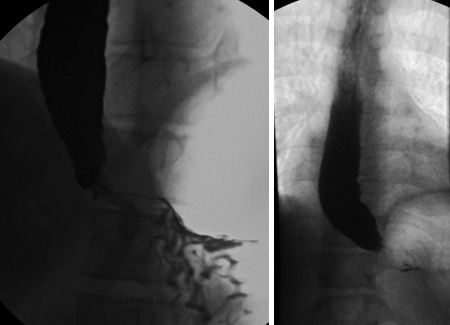

Timed barium oesophagogram

Simple, non-invasive, widely available barium technique for evaluating oesophageal emptying in patients with achalasia.

The films are taken at 1, 2, and 5 minutes after the last swallow of barium; the purpose of 2-minute film is to assess interim emptying.[35][Figure caption and citation for the preceding image starts]: Idiopathic achalasia: barium oesophagograms showing a dilated oesophageal body and a tapering stricture in the distal oesophagus ('bird's beak')From the collection of Dr S. Charous [Citation ends].